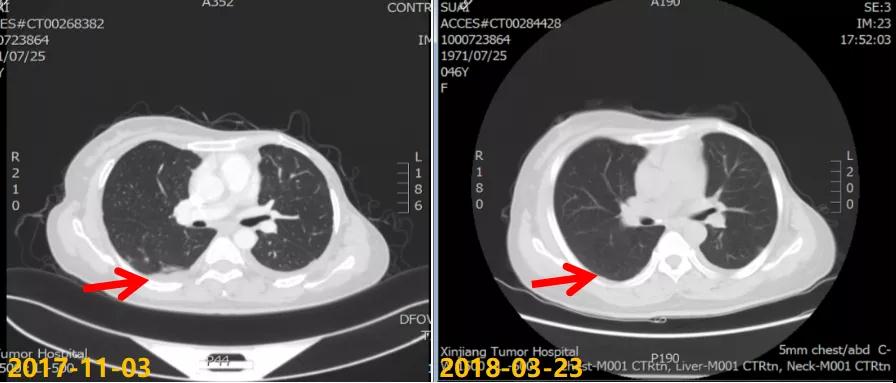

第一次病情进展: 2017-10-22患者因“气喘气憋、呼吸困难20天”就诊我院,胸水超声提示左侧大量胸腔积液,行胸水穿刺引流,查见癌细胞。2017-11-03 CT:两肺多发结节,考虑转移瘤;左侧胸膜斑块状增厚,提示胸膜转移;肝脏多发转移瘤。进一步行肝脏肿块穿刺活检,病理:ER(2+,90%),PR(3+,80%),HER2(2+),Ki-67(+,40%),FISH检测:未观测到基因扩增。

2017-11至2018-03:TX方案6周期(多西他赛120mg d1+卡培他滨1500mg po bid d1-14),化疗期间继续戈舍瑞林3.6mg ih q4w。疗效评估:前四周期略缩小但未达PR,后两周期SD,呼吸道症状明显改善。2018-04行戈舍瑞林3.6mg ih q4w联合氟维司群 500mg im q4w内分泌维持治疗,同时经MDT多学科讨论后行肝脏射频消融术。一线治疗获得36个月PFS。